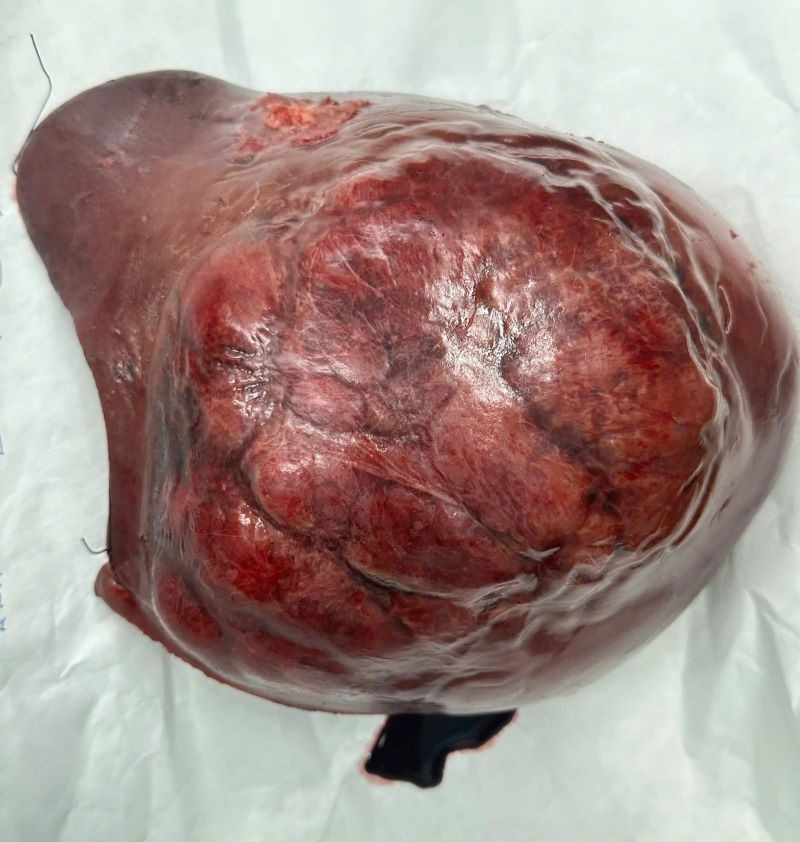

Ở giai đoạn hai, ê kíp phẫu thuật đã thực hiện cắt bỏ toàn bộ gan phải mang khối u, với khối lượng hơn 1,5 kg. Ca mổ thành công, bệnh nhân hồi phục tốt và không gặp biến chứng suy gan do thiếu hụt thể tích gan chức năng.

Gan với khối u gan phải khổng lồ và sau khi cắt bỏ gan phải - Ảnh BVCC

Khối u gan kích thước lớn, chiếm gần toàn bộ gan bên phải sau khi được cắt bỏ - Ảnh BVCC